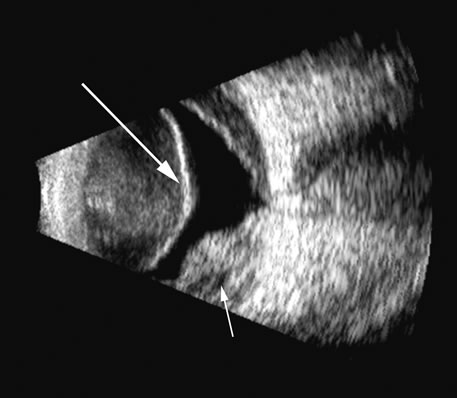

Malignant melanoma varies in its ultrasound presentation from a relatively homogeneous to heterogenous lesion on B-scan. The typical uveal melanoma absorbs sound so that the posterior section is relatively less echoic than the anterior aspect, producing a gradually decreasing amplitude, often to baseline on the A-scan (Fig. 21).

Fig. 21. An ocular tumor at the posterior pole showing the smooth convex border and solid internal reflectants typical of a melanoma.

Melanomas also have varying amounts of melanin, a highly acoustically reflective pigment. As noted, melanomas characteristically show high reflectivity anteriorly, with decreasing reflectance as the sound traverses the tissue. This produces the decreasing amplitude posteriorly in the tumor seen on A-scan and gray-scale B-scan. This effect often enhances the anterior scleral boundary. The posterior tumor border is thus measured as the first “rising” echo from the tumor decline, and it is most easily seen and accurately identified on B-scan.27